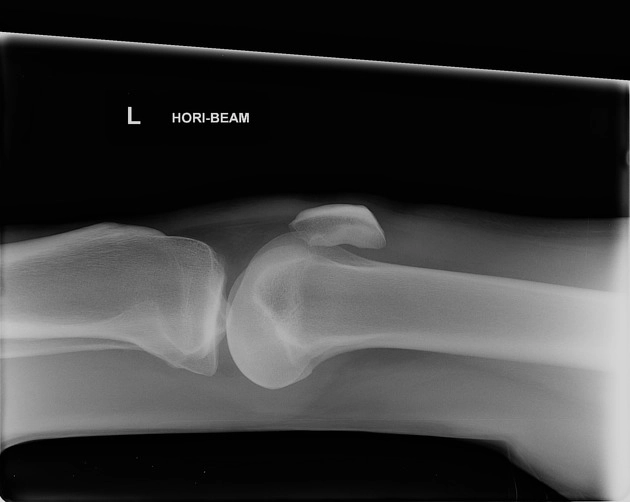

• Tổn thương xương và khớp gối

Gãy mâm chày (Tibial Plateau Fracture)